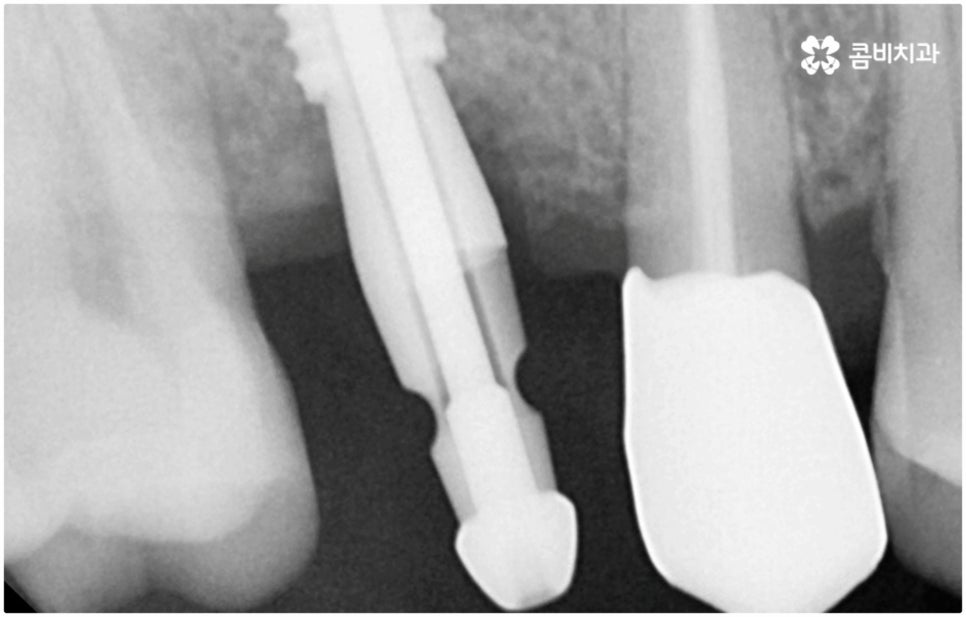

발치후 임플란트 즉시 식립 방식은 다른 임플란트와 달리 치아가 탈락한 빈 자리에 곧바로, 또는 조금 남아있던 뿌리를 뽑은 후 그 자리에 그대로 임플란트를 심기 때문에 공백 기간이 단축될 수 있고 임시치아 제작을 통해 해당 기간 동안 임시 틀니를 사용해야 하는 데서 오는 불편함 및 심미적인 어색함도 해결할 수 있어요. 또한 환자분들의 입장에서 마취 한 번에 발치와 식립 두 가지 과정이 함께 이뤄지기 때문에 통증과 두려움이 감소되고 치과에 내원해야 하는 횟수도 줄어들어 번거로움이 덜 할 수 있습니다.

치아가 빠진 순간부터 이를 받치고 있던 치조골이 서서히 흡수되기 시작하므로 영구치가 빠지고 나서 시간이 많이 지나게 되면 부족한 잇몸뼈 부분을 뼈이식으로 보충해 주는 과정이 추가적으로 들어가야 하지만 이미 뼈가 손상된 경우가 아니라면, 즉시 식립을 하면 그럴 필요가 없는 거예요. 또한 잇몸이 이미 내려앉은 후 수복을 하려면 잇몸 라인이 인위적으로 만들어질 가능성이 높아지는데 치조골 소실이 크게 일어나기 전에 임플란트를 심게 되면 주변 치아 및 잇몸과 보다 조화롭게 맞출 수 있어서 심미적인 부담도 덜 수 있어요.

게다가 발치 부위가 아물면서 자연스럽게 일어나는 인체의 치유 능력을 최대한 이용해 골결합을 유도하므로 부작용 발생 우려가 적고 임플란트의 인공 치근이 환자분들의 잇몸뼈에 좀 더 단단하게 유착될 수 있도록 안정성을 높일 수 있다는 장점도 있는데요.

발치후 임플란트 식립까지 회복 기간을 두지 않고 즉시 심게 되면 원래 치아가 있던 자리를 육안으로 확인한 후 그 자리에 곧바로 식립하므로 보다 정확한 위치를 잡을 수 있다는 장점도 있습니다. 하루 만에 식립과 임시치아까지 장착이 가능하여 간단한 식사도 할 수있다는 점에서 원데이 임플란트라고도 불리는 즉시 식립 방식은 지금까지 알아본 바와 같이 여러 장점을 가지고 있기 때문에 많은 분들이 선호하시고 있는데요.

하지만 여기서 주의하셔야 할 점은 누구나 발치후 임플란트 를 즉시 식립할 수 있는 것이 아니라 바탕이 되는 잇몸뼈의 양이 충분하고 기존에 염증과 같은 잇몸 질환이 없는 분들의 경우에만 이용할 수 있는 방법이기 때문에 3D CT 등 정밀 분석 기계로 환자분들의 상태를 정확하게 진단한 후에 결정해야 한다는 거예요.

임플란트 후 수명을 늘리는 방법에 대해서 문의를 주시는 분들이 많이 있는데요. 지속성을 높이려면 말씀드린 것처럼 치료 자체의 정확성을 신경쓰는 것이 우선시 되어야 할 거예요. 즉 환자분들의 상황을 꼼꼼하게 검진하고 이에 맞는 방법으로 정확하게 식립하는 치과에서 임플란트 수술을 진행하는 것이 무엇보다 중요하다고 할 수 있습니다. 이를 위해서 환자분들의 잇몸뼈 두께나 밀도를 면밀하게 살필 수 있는 3D CT 기계를 갖추고 처음부터 끝까지 책임 진료하는 숙련된 의료진 분들과 함께 하시는 게 좋을 거예요.

이때 환자분들 각각의 정밀한 맞춤 계획을 세우고 이를 무리하지 않게 진행하기 위해서는 해당 치아의 잇몸뼈 상황 뿐 아니라 주변 치아 구조, 신경 위치 그리고 환자분들의 전체적인 구강 내 건강 상태 (치주 질환 여부 등) 를 자세하게 관찰하고 그 밖에 연령이나 기존 전신 질환 여부 (상용하는 약이 있는지 여부도 포함) 등 모든 부분을 충분한 상담을 통해 빠짐없이 파악하며 행여 중간중간 돌발 상황이 발생해도 침착하게 해결해 나가는 것이 중요하기 때문에 담당 의료진에게 굉장히 높은 수준의 기술력과 풍부한 노하우가 요구됨을 짐작할 수 있는데요. 이와 같이 매우 고난도 진료인 발치후 임플란트 시술을 보다 안정적으로 진행하기 위해서는 정밀 장비 보유 여부 및 의료진의 경력과 노하우를 철저하게 체크해 보시고 치과를 신중하게 선택하실 필요가 있어요.